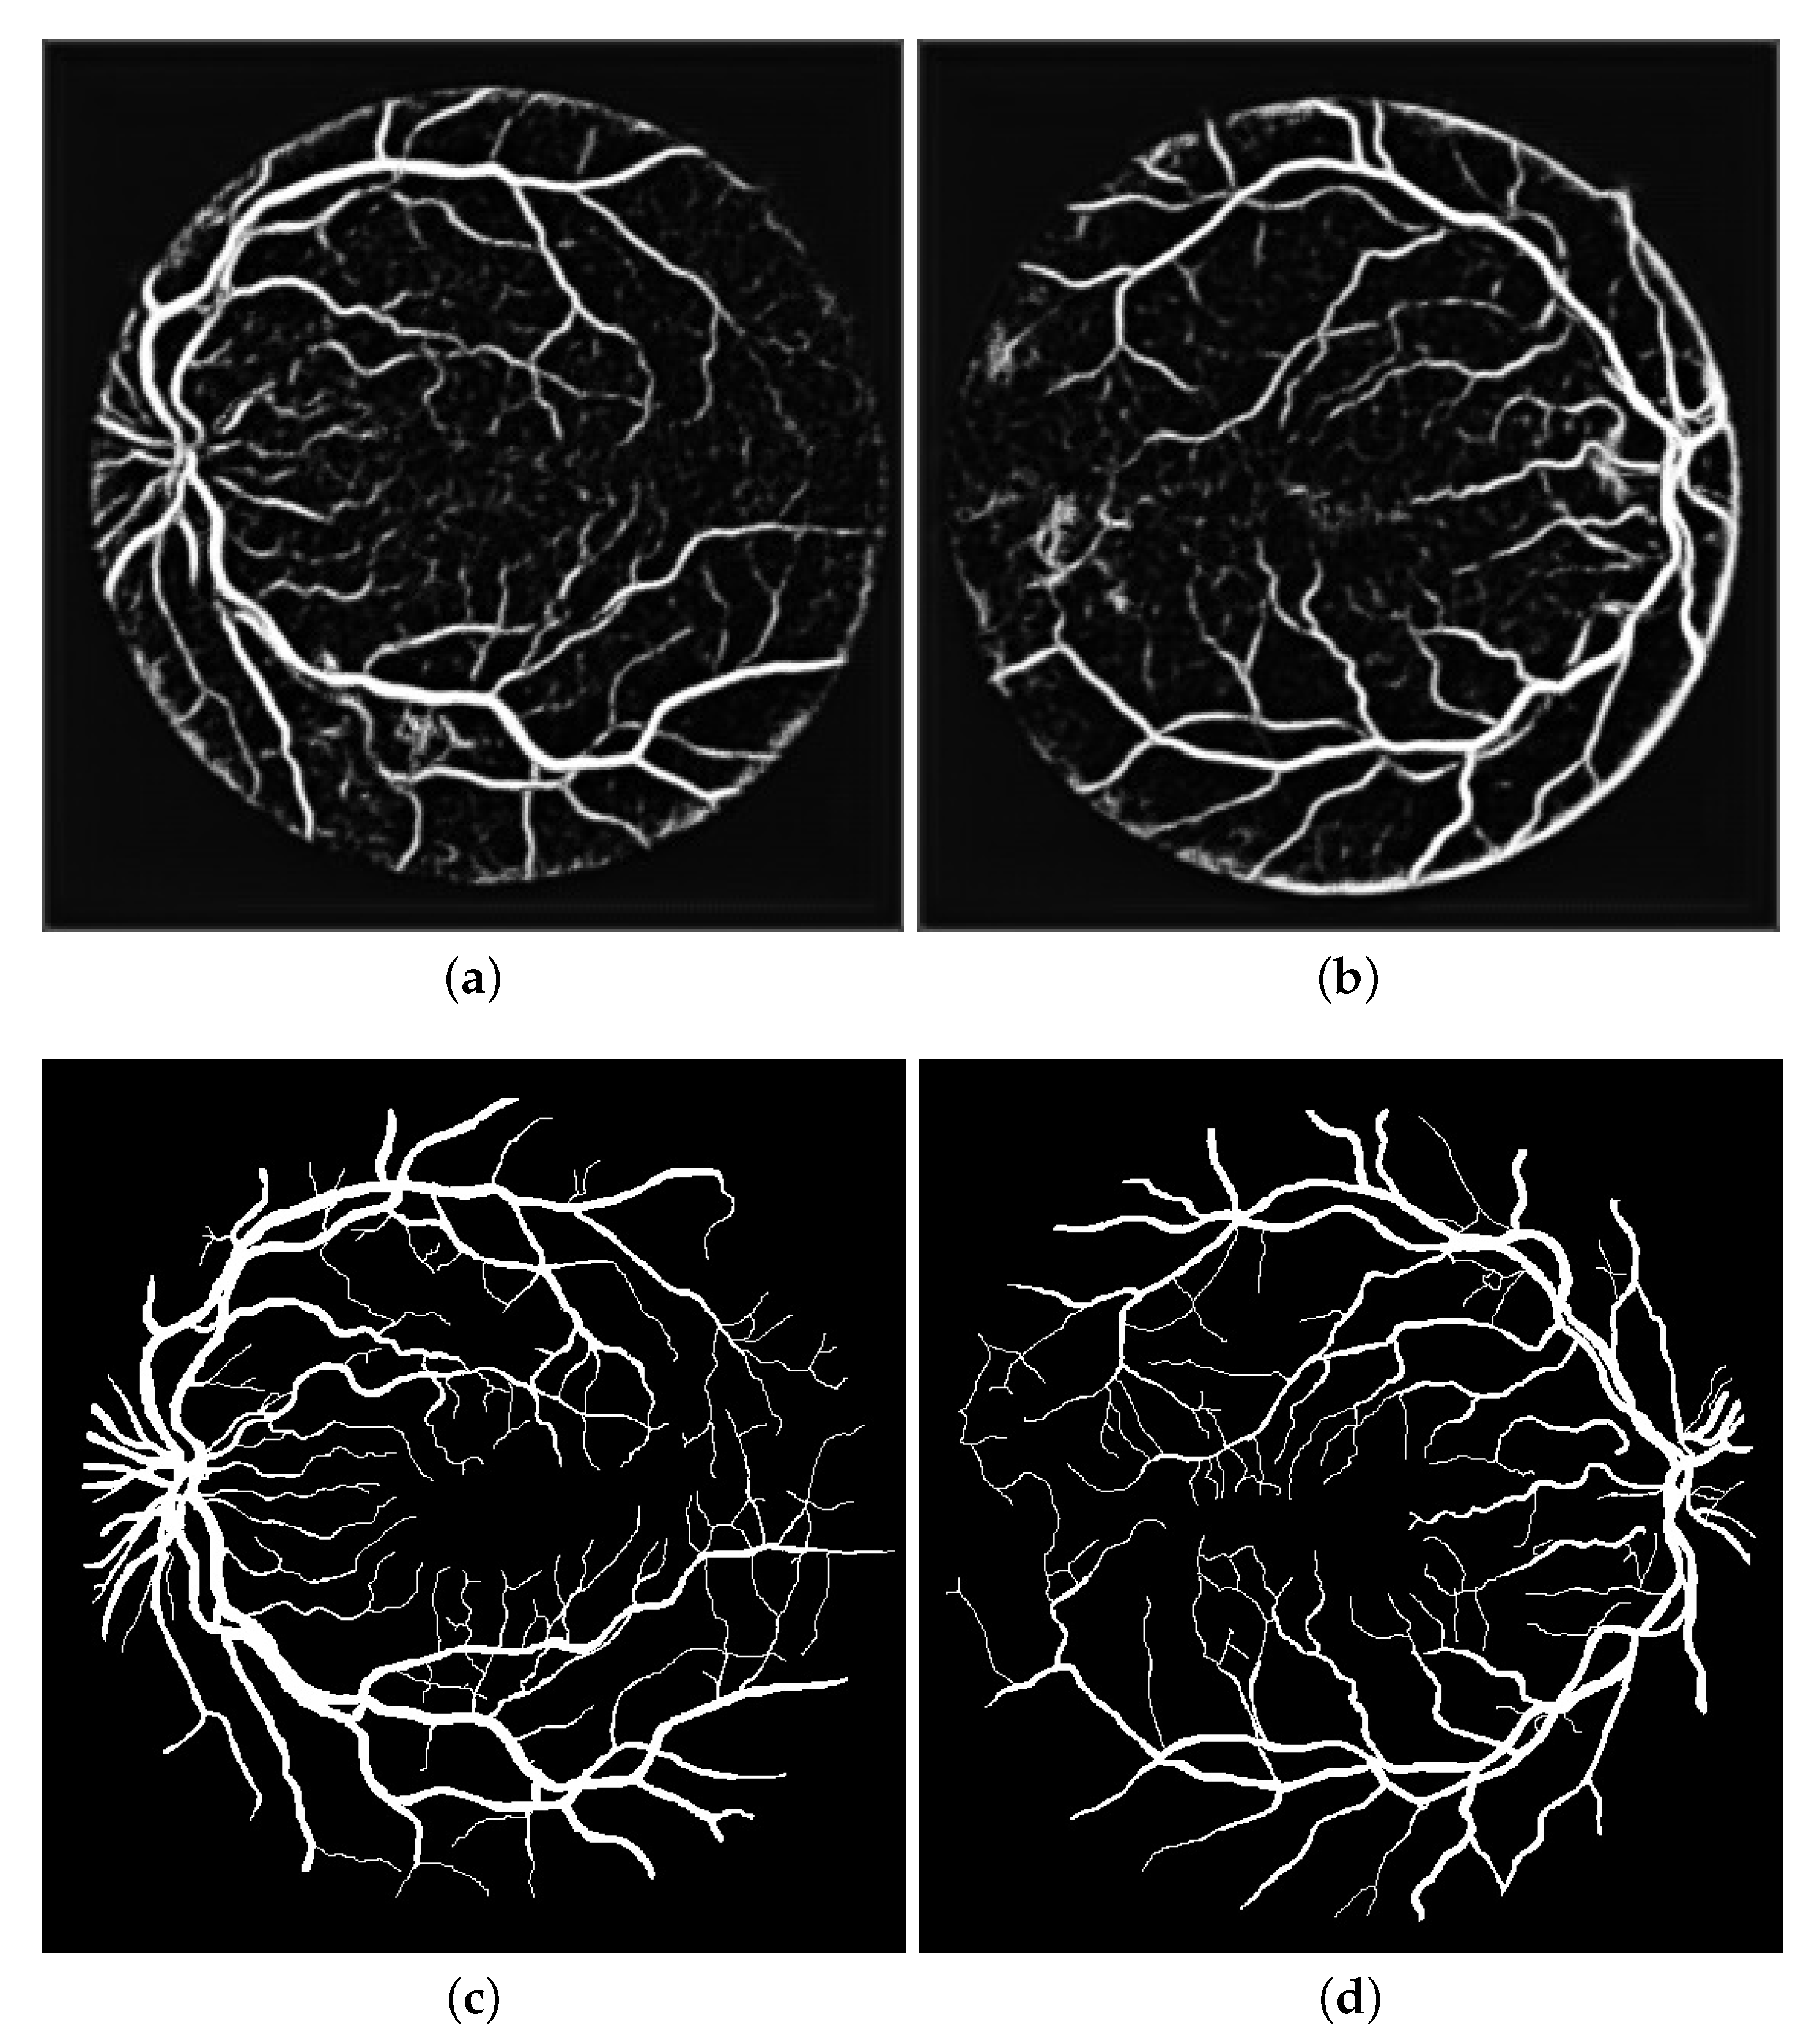

- The fourth stage contained the coherence of the vessels in particular the tiny vessels. This is an important step to obtain a well-segmented image of vessels and increase the sensitivity of vessel detection. The different anisotropic-oriented diffusion filtering schemes are tested to obtain a well-performed filtering scheme. The optimized anisotropic-oriented diffusion filtering scheme addressed the problem of uneven vessel intensity and resulted in a well-coherent image of the vessels.

4.1.2. Impact of the Coherence of the Retinal Blood Vessels